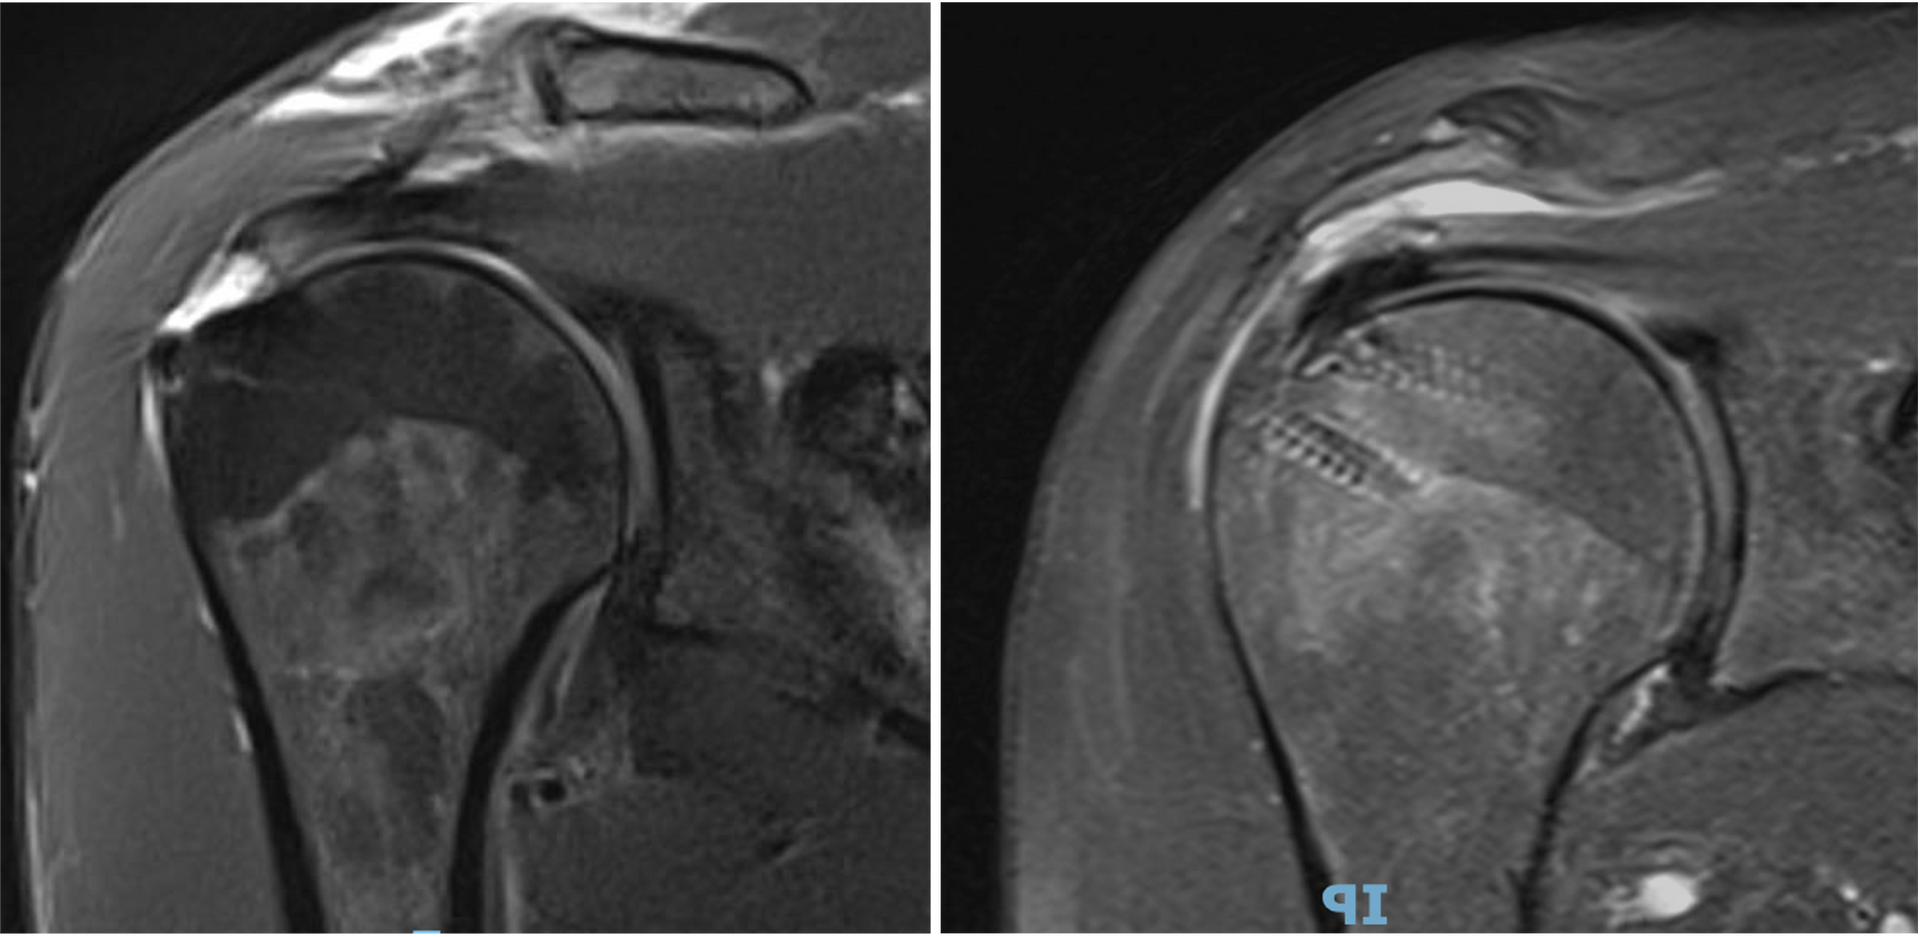

nas pessoas com instabilidade atraumática, multidirecional, com hiperfrouxidão ligamentar, a luxação pode ocorrer sem nenhuma lesão estrutural. Nesses casos, os exames de imagem mostram a

cápsula articular com maior volume do que o habitual e maior elasticidade ligamentar.

Extensão das lesões:

a avaliação das lesões ligamentares e ósseas, principalmente por ressonância magnética, é importante para a indicação cirúrgica; rupturas extensas do lábio da glenoide ou lesões ósseas acometendo a borda da glenoide

(lesão de Bankart ósseo)

são fatores considerados para a indicação do tratamento cirúrgico